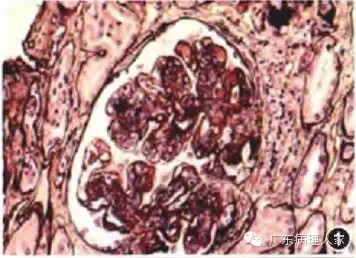

1.肾活检的病理诊断必须密切联系临床,虽然任何病理检查均须与临床表现联系来思考,但对肾活检病理诊断而言,这一点更为重要。因为同一种病理表现可能对应着截然不同的临床肾脏病,由于临床治疗方法不同,一旦误诊,将造成不良后果,如一种以系膜细胞和内皮细胞弥漫增生为特点的肾小球病变,有急性链球菌感染后肾小球肾炎、病毒感染后肾小球肾炎、活动性弥漫增生性狼疮性肾炎(图1)、IgA肾病(图2)、过敏性紫癜性肾炎等多种可能,决定性因素是临床表现和化验指征。另者,同一临床肾脏疾病可有不同的病理表现,仍以临床确诊为系统性红斑狼疮而导致的狼疮性肾炎为例,可分为轻微病变型、轻度系膜增生型、局灶增生型、弥漫球性增生型、弥漫节段增生型、膜增生型、新月体型、膜型、增生硬化和硬化型多种病理类型。所以,从事肾活检病理诊断的病理医师,一定要具备必要的临床肾脏疾病知识。

图1 毛细血管内增生性狼疮性肾炎,肾小球内皮细胞和系膜细胞弥漫增生 PASM染色 高倍放大